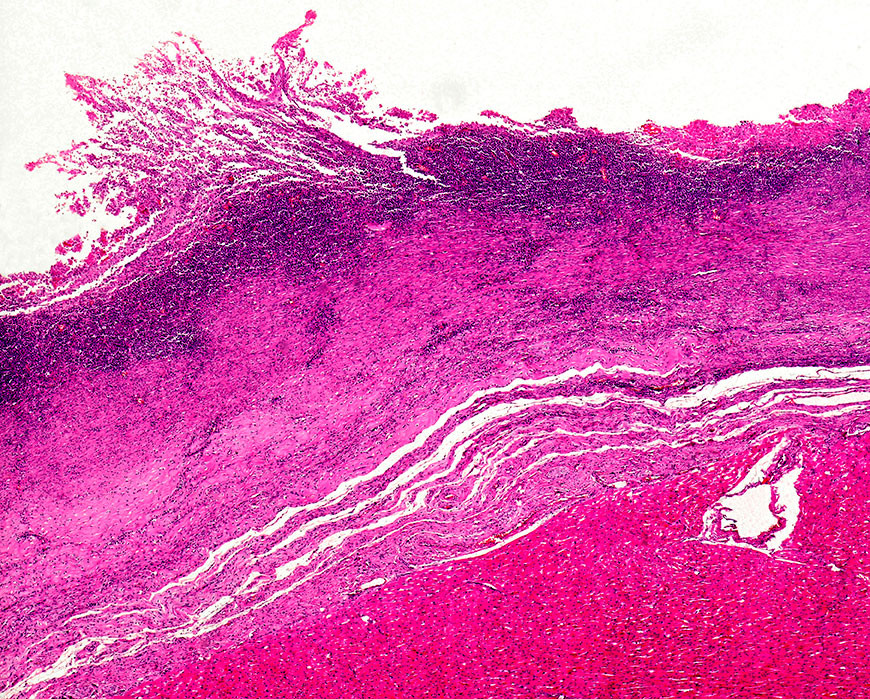

Kardiomyopati vist ved lysmikrografi av hjertemuskel. Foto: Science Photo Library / NTB